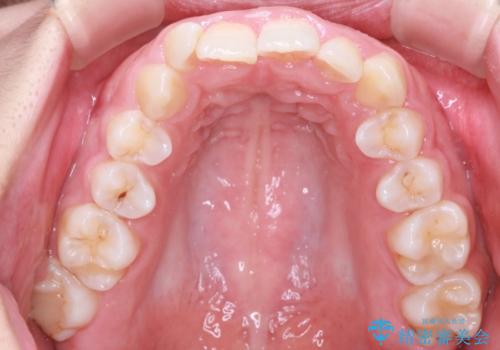

- 患者様は、ディープバイト(深い噛み合わせ)と、咬合平面の左下がりが気になるとのことでご来院されました。診断の結果、非抜歯で治療可能と判断し、透明なマウスピース型矯正装置「インビザライン」を用いる方針としました。治療では、歯列全体の調整を行いながら、咬合平面の水平化を重点的に進める計画を立案しました。2年間で計画的にマウスピースを交換し、左右のバランスと噛み合わせの改善を目指しました。

ディープバイトの矯正は、噛み合わせが深くなりがちなため、細心の注意を払いながら進める必要があります。本症例では、奥歯の高さを調整しつつ前歯の噛み合わせを浅くすることで、全体の咬合バランスを整えました。また、咬合平面の左下がりを修正する過程で、歯列に不均等な力がかからないよう、インビザラインのアタッチメント配置を最適化しました。患者様には装着時間を守っていただき、治療が計画通り進むよう協力をお願いしました。治療終了後には、リテーナーを装着して安定性を確保しました。